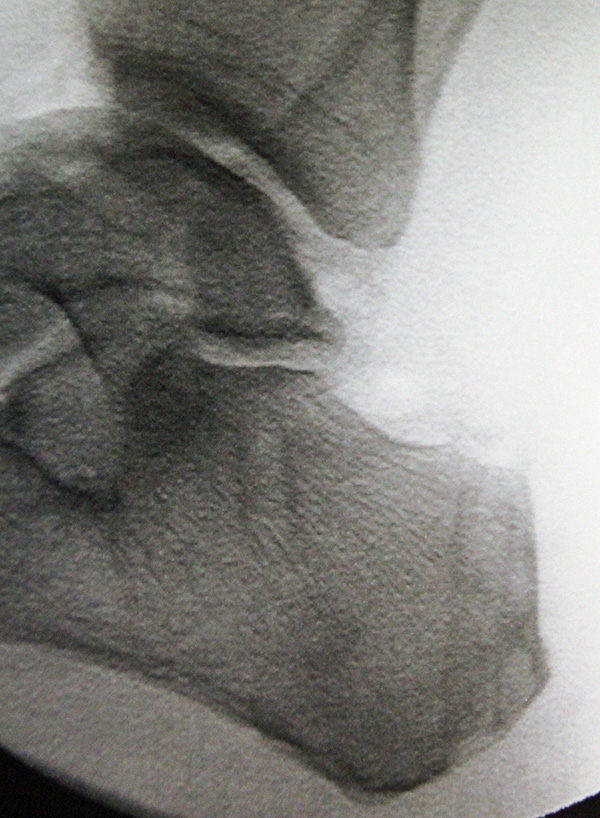

• Seitliches Röntgenbild des Kalkaneus.

Nach korrekter Platzierung des Zielbügels, wird die Bohrhülse des Zielgeräts über eine kleine Stichinzision plantar zentral an der Ferse bis an den Kalkaneus geschoben. Durch die Hülse wird ein K-Draht bis durch die Gegenkortikalis eingebracht. Als nächstes werden die Hülse und der Zielbügel entfernt und der Draht wird mit einem kanülierten Bohrer bis durch die Gegenkortikalis überbohrt, so dass ein durchgehender Knochentunnel entsteht. Der Durchmesser des Bohrers wird vorher anhand des gemessenen Sehnendurchmessers bestimmt und sollte 0,5mm größer als der Sehnendurchmesser gewählt werden, damit bei der späteren Fixation der Sehne genügend Platz für eine Interferenzschraube bleibt (Beispiel: Sehnendurchmesser 6mm, Bohrer 6,5mm). Die Positionierung des K-Drahts und die Lage des Bohrkanals sollten mit einem Bildverstärker im seitlichen Strahlengang intraoperativ kontrolliert werden.

• Fehlpositionierung des Bohrkanals: Um eine Fehlplatzierung des kalkanearen Bohrkanals zu vermeiden, ist eine radiologische Überprüfung der Positionierung des K-Drahts intraoperativ im seitlichen und axialen Strahlengang sinnvoll. Hiermit kann sowohl die mediolaterale Positionierung (axialer Strahlengang) als auch Ein- und Außtrittsstelle (lateraler Strahlengang) sicher identifiziert werden. Darüber hinaus ist es sinnvoll, den Bohrkanal sowie die sichere Lage des Führungsdrahts vor Eindrehen der Interferenzschraube während der OP mit dem Bildverstärker zu dokumentieren.